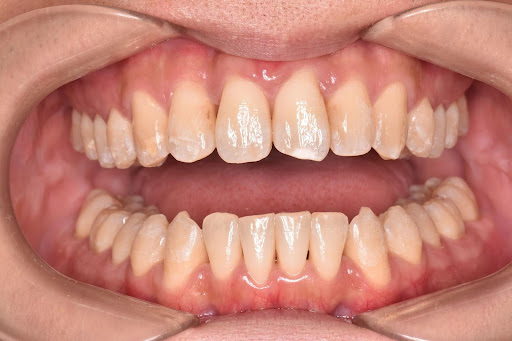

【症例写真】豊富な経験に基づき、歯の重なりやアーチの形状を美しく改善します。

After